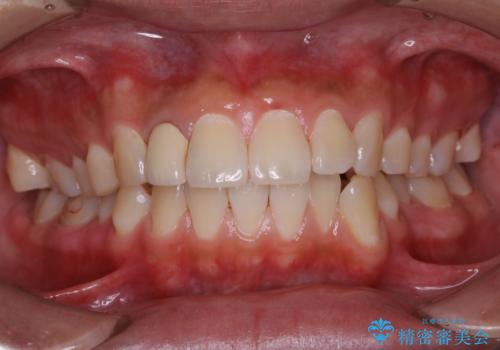

前歯の歯肉退縮 歯周形成外科(歯冠側移動術)